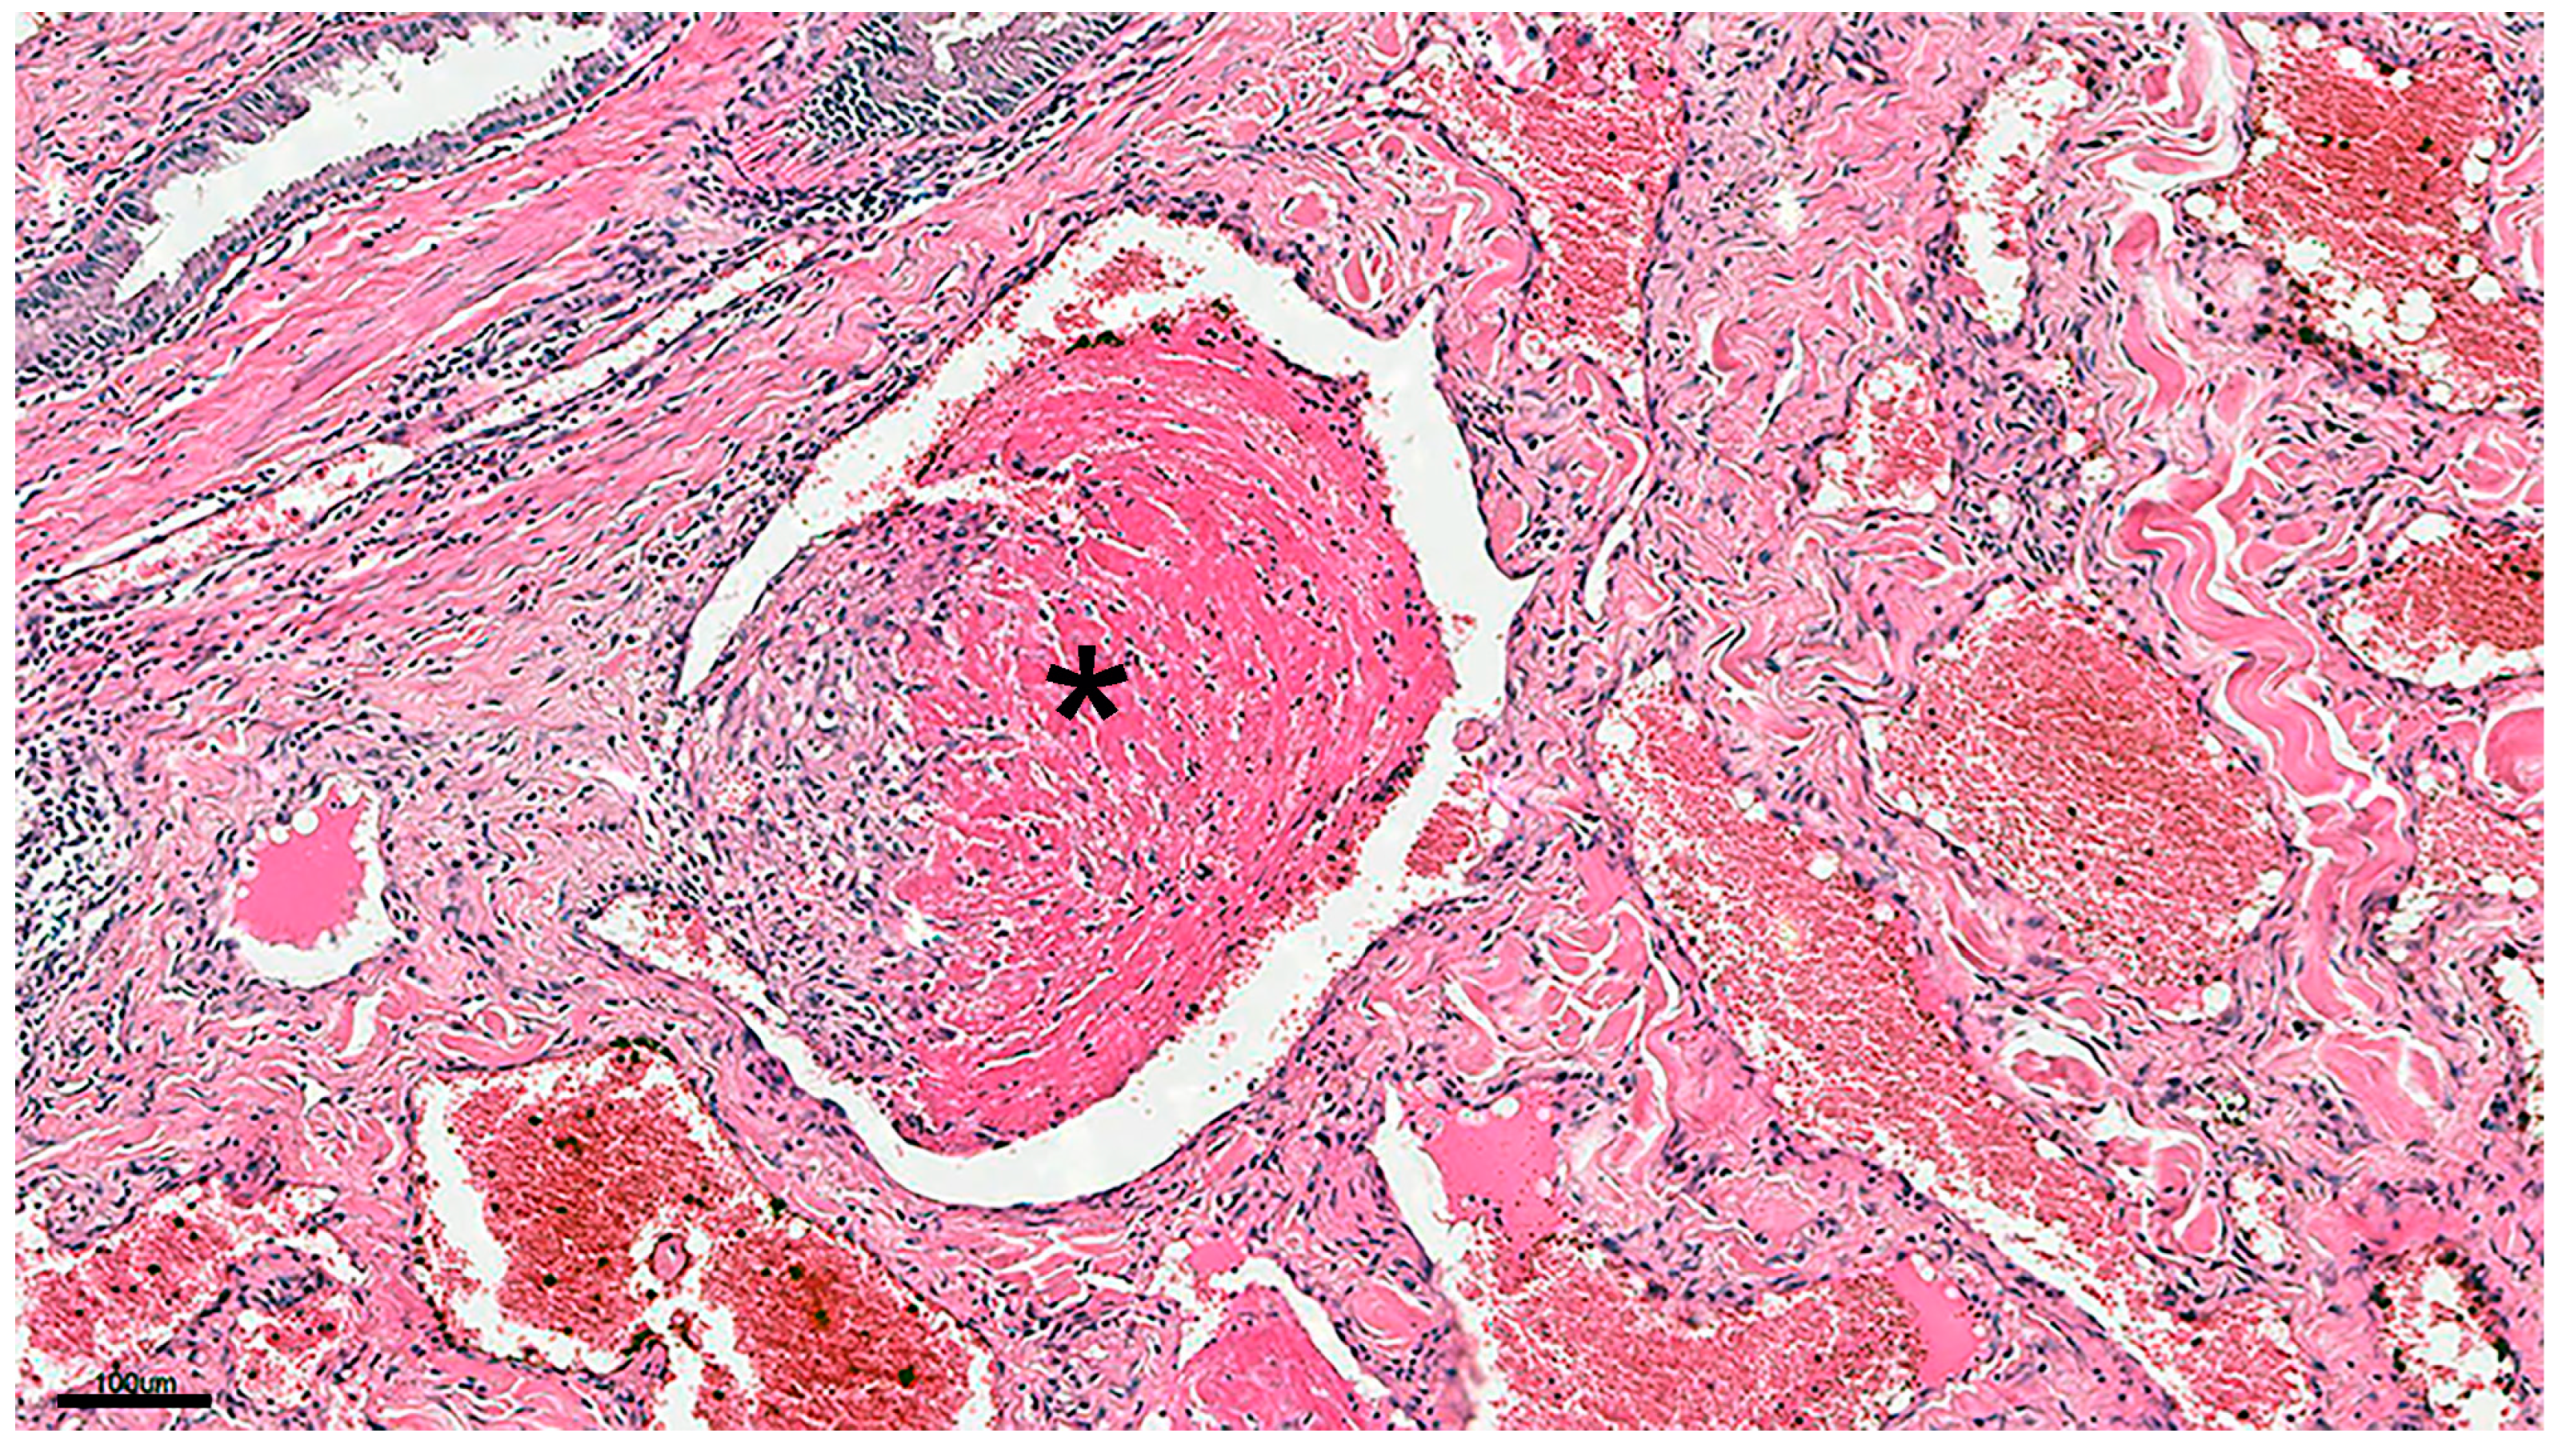

3.1. Hemangiomas

3.1.2. Histopathology

3.1.3. Immunohistochemistry